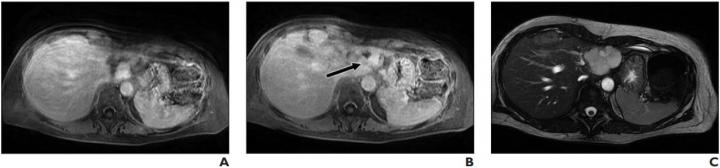

image: Lesion was originally reported as indeterminate enhancing mass, and outside report recommended biopsy. Classic features of benign hemangioma are shown. Error was attributed to faulty reasoning. A, Axial MR image obtained 5 minutes after contrast agent administration shows peripheral nodular discontinuous enhancement. B, Axial MR image obtained 10 minutes after contrast agent administration shows centripetal progression of enhancement (arrow). C, Axial fast imaging employing steady-state acquisition (FIESTA) MR image shows lesion is homogeneously hyperintense compared with liver parenchyma.

The most common error type contributing to both overall and primary discrepancy was faulty reasoning (a cognitive error characterized by misidentifying an abnormality), which occurred in 34.3% of the total discrepancies (95% CI, 29.0- 40.0%) and 37.8% of the primary discrepancies.